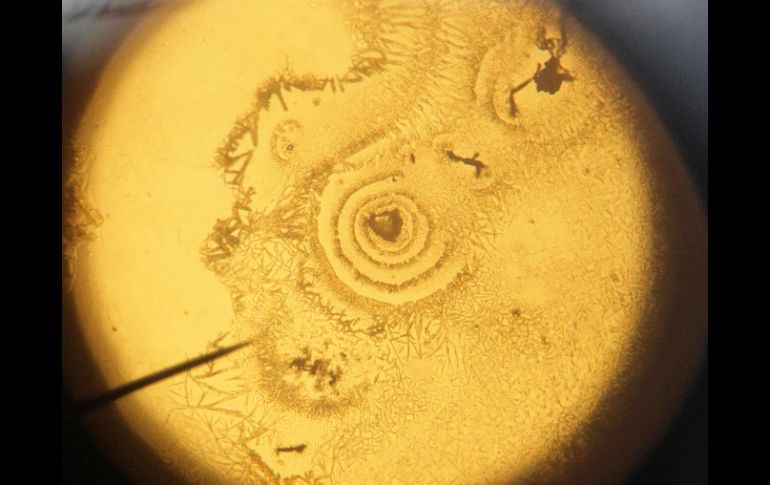

Tecnología | Este avance abre nuevas vías para el tratamiento de enfermedades degenerativas Generan cartílago a partir de células madre humanas Este avance abre nuevas vías para el tratamiento de enfermedades degenerativas de las articulaciones Por: EFE 11 de mayo de 2015 - 10:13 hs La investigación demuestra que las células madre pueden producir 'in vivo' cartílago articular estable. EFE / ARCHIVO LONDRES, INGLATERRA (11/MAY/2015).- La regeneración de cartílago articular a través del trasplante de células madre humanas abre nuevas vías para el tratamiento de enfermedades degenerativas de las articulaciones, según un estudio divulgado por la revista británica Nature. La investigación, desarrollada por científicos de la University Health Network de Toronto (Canadá), demuestra que las células madre pluripotentes (neoblastos), capaces de convertirse en cualquier tipo de células del organismo, pueden "producir 'in vivo' cartílago articular estable". En el texto, los autores destacan que estudios anteriores han descrito la diferenciación de las células madre pluripotentes del "linaje de la condrogénesis", si bien no han llegado a constatar que la formación de condrocitos (células que se encuentran en los cartílagos) capaces de "producir 'in vivo' cartílago articular estable". "Aquí demostramos que la activación de la vía de la TGFb (de la familia de los factores de crecimiento) en progenitores condrogénicos derivados de células madre pluripotentes promueve el desarrollo eficiente de condrocitos articulares que pueden formar 'in vitro' o 'in vivo' tejido cartilaginoso estable", sostienen los científicos. Por contra, precisan, los condrocitos especificados por una proteína formadora de hueso, la llamada "Bone morphogenetic protein 4 (BMP4)", presentan señales "características de hipertrofia" y "generan tejidos cartilaginosos que inician el proceso 'in vivo' de osificación endocondral". "Estos descubrimientos -señalan- ofrecen una vía eficiente y libre de suero para la generación común de condrocitos articulares a partir de células madre pluripotentes capaces de tratar enfermedades de las articulaciones y desarrollar terapias celulares para curarlas". El estudio explica que en "enfermedades debilitadoras", como la osteoporosis, la degeneración del cartílago articular conduce a la "activación inapropiada de las vías de señalización", lo cual puede provocar hipertrofia, "apoptosis (muerte celular) de los condrocitos articulares" y "la aparición de osteofitos" (calcificaciones). Dado que el cartílago articular dañado tiene poca capacidad para regenerarse por sí mismo, los expertos recurren a las "terapias de sustitución" porque son la "únicas que pueden tratar a pacientes con osteopatía avanzada". "La sustitución de condrocitos articulares o cartílago articular con células o tejidos generados 'in vitro' ofrece una estrategia alternativa al recambio de toda la articulación, el método actual preferido", afirman los científicos. Temas Estudios científicos Ciencia médica Células madre Lee También ¡Súbete, Glinda, súbete! Los memes tras invitación de Universal para "Las Perdidas" "Las Perdidas" serán anfitrionas de "La fiesta de disfraces mágicos Wicked" Estudio chino revela una mutación que eleva riesgo de alzhéimer NASA confirma si el cometa 31/ATLAS amenaza la vida en la Tierra o no Recibe las últimas noticias en tu e-mail Todo lo que necesitas saber para comenzar tu día Registrarse implica aceptar los Términos y Condiciones